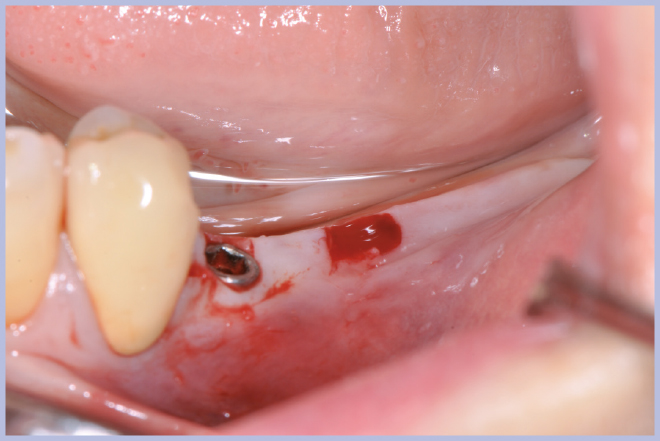

Viene quindi richiesto al tecnico di modificare in laboratorio la mascherina radiologica mediante il posizionamento delle boccole di guida adatte agli impianti da posizionare (Exacone® 6.5 e Exacone® 3,3×8) in asse con gli analoghi del modello Master 3D ed eliminando il repere radiologico standardizzato, trasformandola così nella dima chirurgica (Figg. 14, 15). Si procede quindi alla prova della mascherina sulla paziente per verificarne la stabilità e la corrispondenza esatta con il modello Master 3D (Fig. 16). La seduta chirurgica con tecnica flapless, guida chirurgica e Frese Zero1 dedicate non presenta alcuna difficoltà ; al termine dell’inserimento si posizionano sugli impianti tappi di guarigione bassi per permettere loro di guarire con tecnica sommersa (Figg. 17-27). Si effettua nella stessa seduta una CBCT che dimostra che la posizione clinica degli impianti risulta sovrapponibile a quella progettata dagli Autori (Figg. 28-30).

- Figg. 17, 18 – Passaggio dei mucotomi guidati dalla mascherina chirurgica

- Fig. 18